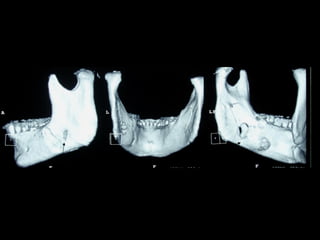

Eliminación de focos sépticos en bloque en paciente con osteitis

mandibular crónica

Osteitis

Imagen microscópica de osteitis, inicialmente existe una etapa de

osteoclastosis seguida por regeneración. No siempre el hueso

regenera en su totalidad y sigue el curso de cualquier inflamación

dejando un area de tejido fibroso que con el tiempo puede

calcificarse (hueso denso)

Manejo con antibióticos obligado

Revisión periódica